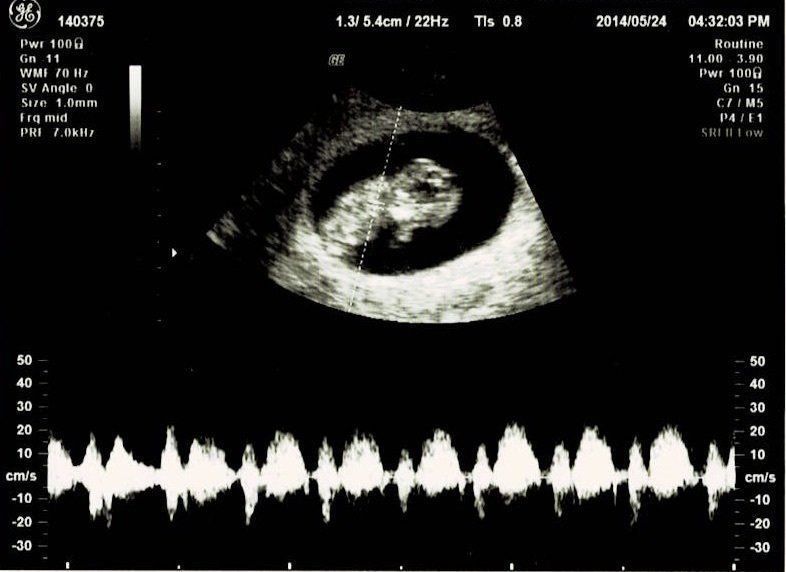

この日は、BPD(頭の左右幅)、AC(おなかの周りの長さ)、FL(太ももの骨の長さ)を測って、赤ちゃんの育ちぐあいを見てくれました。このエコーは足の骨を測っているところです。足の指らしき骨も見えます。先生がスムーズに赤ちゃんの頭やおなか、足を探すのが面白く、測っている最中のエコーもずっと眺めていました。